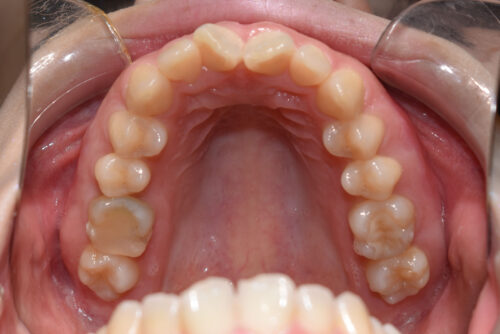

下の歯が 全く見えない状態で

上下の歯が 翼のように ガタついて(翼状捻転)いる

状態でした。